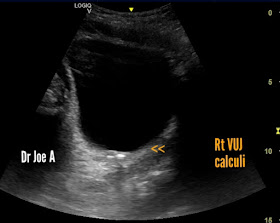

Rt VUJ calculi, there are 2 of them.

A poor twinkle artefact present 👆👆

Right ureteral jet of urine visualized 👆 suggesting partial or little obstruction.